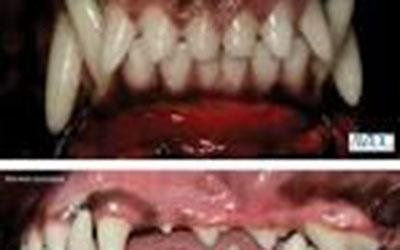

La malattia parodontale è un'infiammazione dei tessuti moli circostanti dei denti e in fase avanzata forma la placca prodotta da batteri, tartaro calcificato. Nelle fasi finali della malattia parodontale, i tessuti circostanti del dente sono danneggiati, l'osso erode e il dente si allenta che è estremamente doloroso e scomodo per animale.Cattive condizioni di salute dentale può portare alla diminuzione dell'appetito, mancanza di energia, cattivo odore dalla bocca.

La pulizia dei denti,rimozione dei denti amalati sarà necessaria per gestire una situazione cosi grave.

Le statistiche ci dicono che oltre 70 % dei gatti e oltre 80 % dei cani sono affetti delle patologie dentarie e gengivali già dell’età di tre anni. Medico specializzato in odontostomatologia veterinaria che dispone di attrezzatura dedicata si occupa di tutti problemi che provoca la malattia dentale:ablazione del tartaro,estrazione dei denti malati,fratturati ,denti da latte o estrazione di tutti i denti nel caso di stomatite ulcerativa nel gatto,cure endodontali.